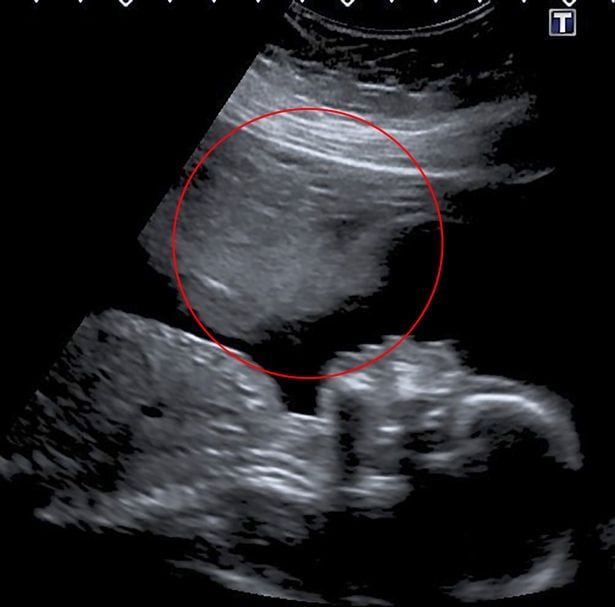

Allí le informaron que tenía un gran hematoma, y que había crecido junto a su bebé, por lo que necesitaría controles cada dos semanas. Luego, a los 14 días la mujer sufrió otra hemorragia, pero sus preocupaciones se calmaron cuando los médicos le dijeron que el escáner mostraba latidos cardíacos saludables y un bebé en crecimiento.

“En mi exploración de 16 semanas, el hematoma finalmente se estaba reduciendo y en mi exploración de 18 semanas se redujo a la mitad de su tamaño anterior”, continuó.

Afortunadamente, el panorama comenzó a cambiar paulatinamente: dejó de sangrar a las 19 semanas y en la eco de las 20 semanas la imagen reveló algo junto al bebé en gestación, que la mujer definió como el ‘ángel de la guarda’: “No estaba fuera de peligro, pero definitivamente podía respirar un poco más”.